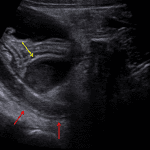

- Superficial to this is a 2 x 2.5 cm ovoid hypoechoic structure which appears separate from the adjacent bowel and shows no internal vascularity

- Surrounding inflammatory changes in the right lower quadrant

Superficial to this is a 2 x 2.5 cm ovoid hypoechoic structure which appears separate from the adjacent bowel and shows no internal vascularity, concerning for a periappendiceal abscess.